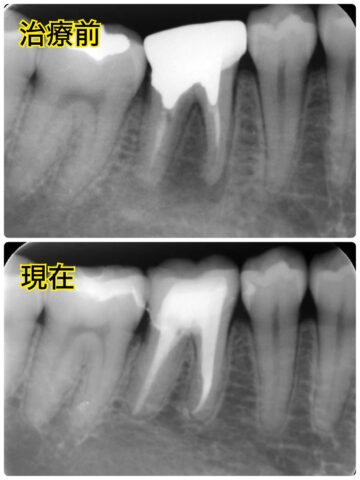

そして、最初に治療した右下奥の歯は矯正用仮歯からオールセラミックスへ✨

オールセラミックスを入れる前のCTで、溶けてしまっていた骨がしっかりと回復しているのが分かります😊

↓オールセラミックスを入れた後のレントゲン写真での比較です。